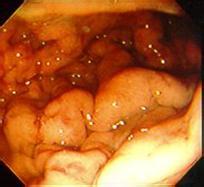

我們都知道,檢查是治療的關鍵,只有確定了反流性威嚴的程度,胃腸粘膜受損的程度,是否出現潰瘍,水腫等癥狀,對于后續的治療是十分重要的,而這些不是普通機器就能檢查出來的,需要進行胃鏡檢查,由于以往人們對于胃鏡檢查痛苦的懼怕,很多患者選擇逃避檢查,導致了病情無法得到全面的治療。